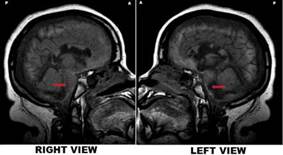

Preservation of intracranial structures

A striking finding was the preservation of intracranial structures both in the brainstem and cerebral hemispheres, which was observed nine months after cardiac arrest resulting in severe brain injury. 13 It has been extensively described that a brain-dead patient lacks cerebral blood flow (CBF). 15,16

Wijdicks recently studied a series of brain-dead patients and documented that no distinguishing neuropathological BD features were found, probably because timing to brain fixation has been reduced as a consequence of timely organ transplant protocols. 21 This was not the case in Jahi McMath because an MRI study was performed nine months after the initial insult. 13

Therefore, the first argument against the diagnosis of BD, nine months after the initial diagnosis is the preservation of intracranial structures. Shewmon has reported a series of brain-dead patients with extended somatic survival. 23-25 He expressly referred to Repertinger et al.'s case of a 4-year-old child diagnosed as brain-dead after bacterial meningitis and was then put on a ventilator for 19 years. The autopsy revealed a 750 g calcified intracranial spherical structure and a calcified shell containing grumous material and cystic spaces with no recognizable neural elements grossly or microscopically. 26 Nothing similar was found in this patient's MRI sequences, despite a vast brain insult. Hence, this fact contradicts BD diagnosis in this patient. 13,14,27

As previously noted, Jahi McMath's mri demonstrated a large lesion in the pons. Hence, several reasons might explain the intermittent conscious responses in this patient, including the relative intactness of the upper brainstem, thalamus, and cortex and the partial sparing of the mesopontine tegmental reticular formation. She might also have preserved its connections to the thalamocortical or its ventral pathway to the cortico-cortical projection systems, and parts of the associative cerebral cortices. 6,13,42 Therefore, Walter et al. were not far from the truth when they hypothesized that “a brainstem lesion may cause an apneic total locked-in syndrome, a rare syndrome with preserved capability for consciousness, mimicking brainstem death.”4,45